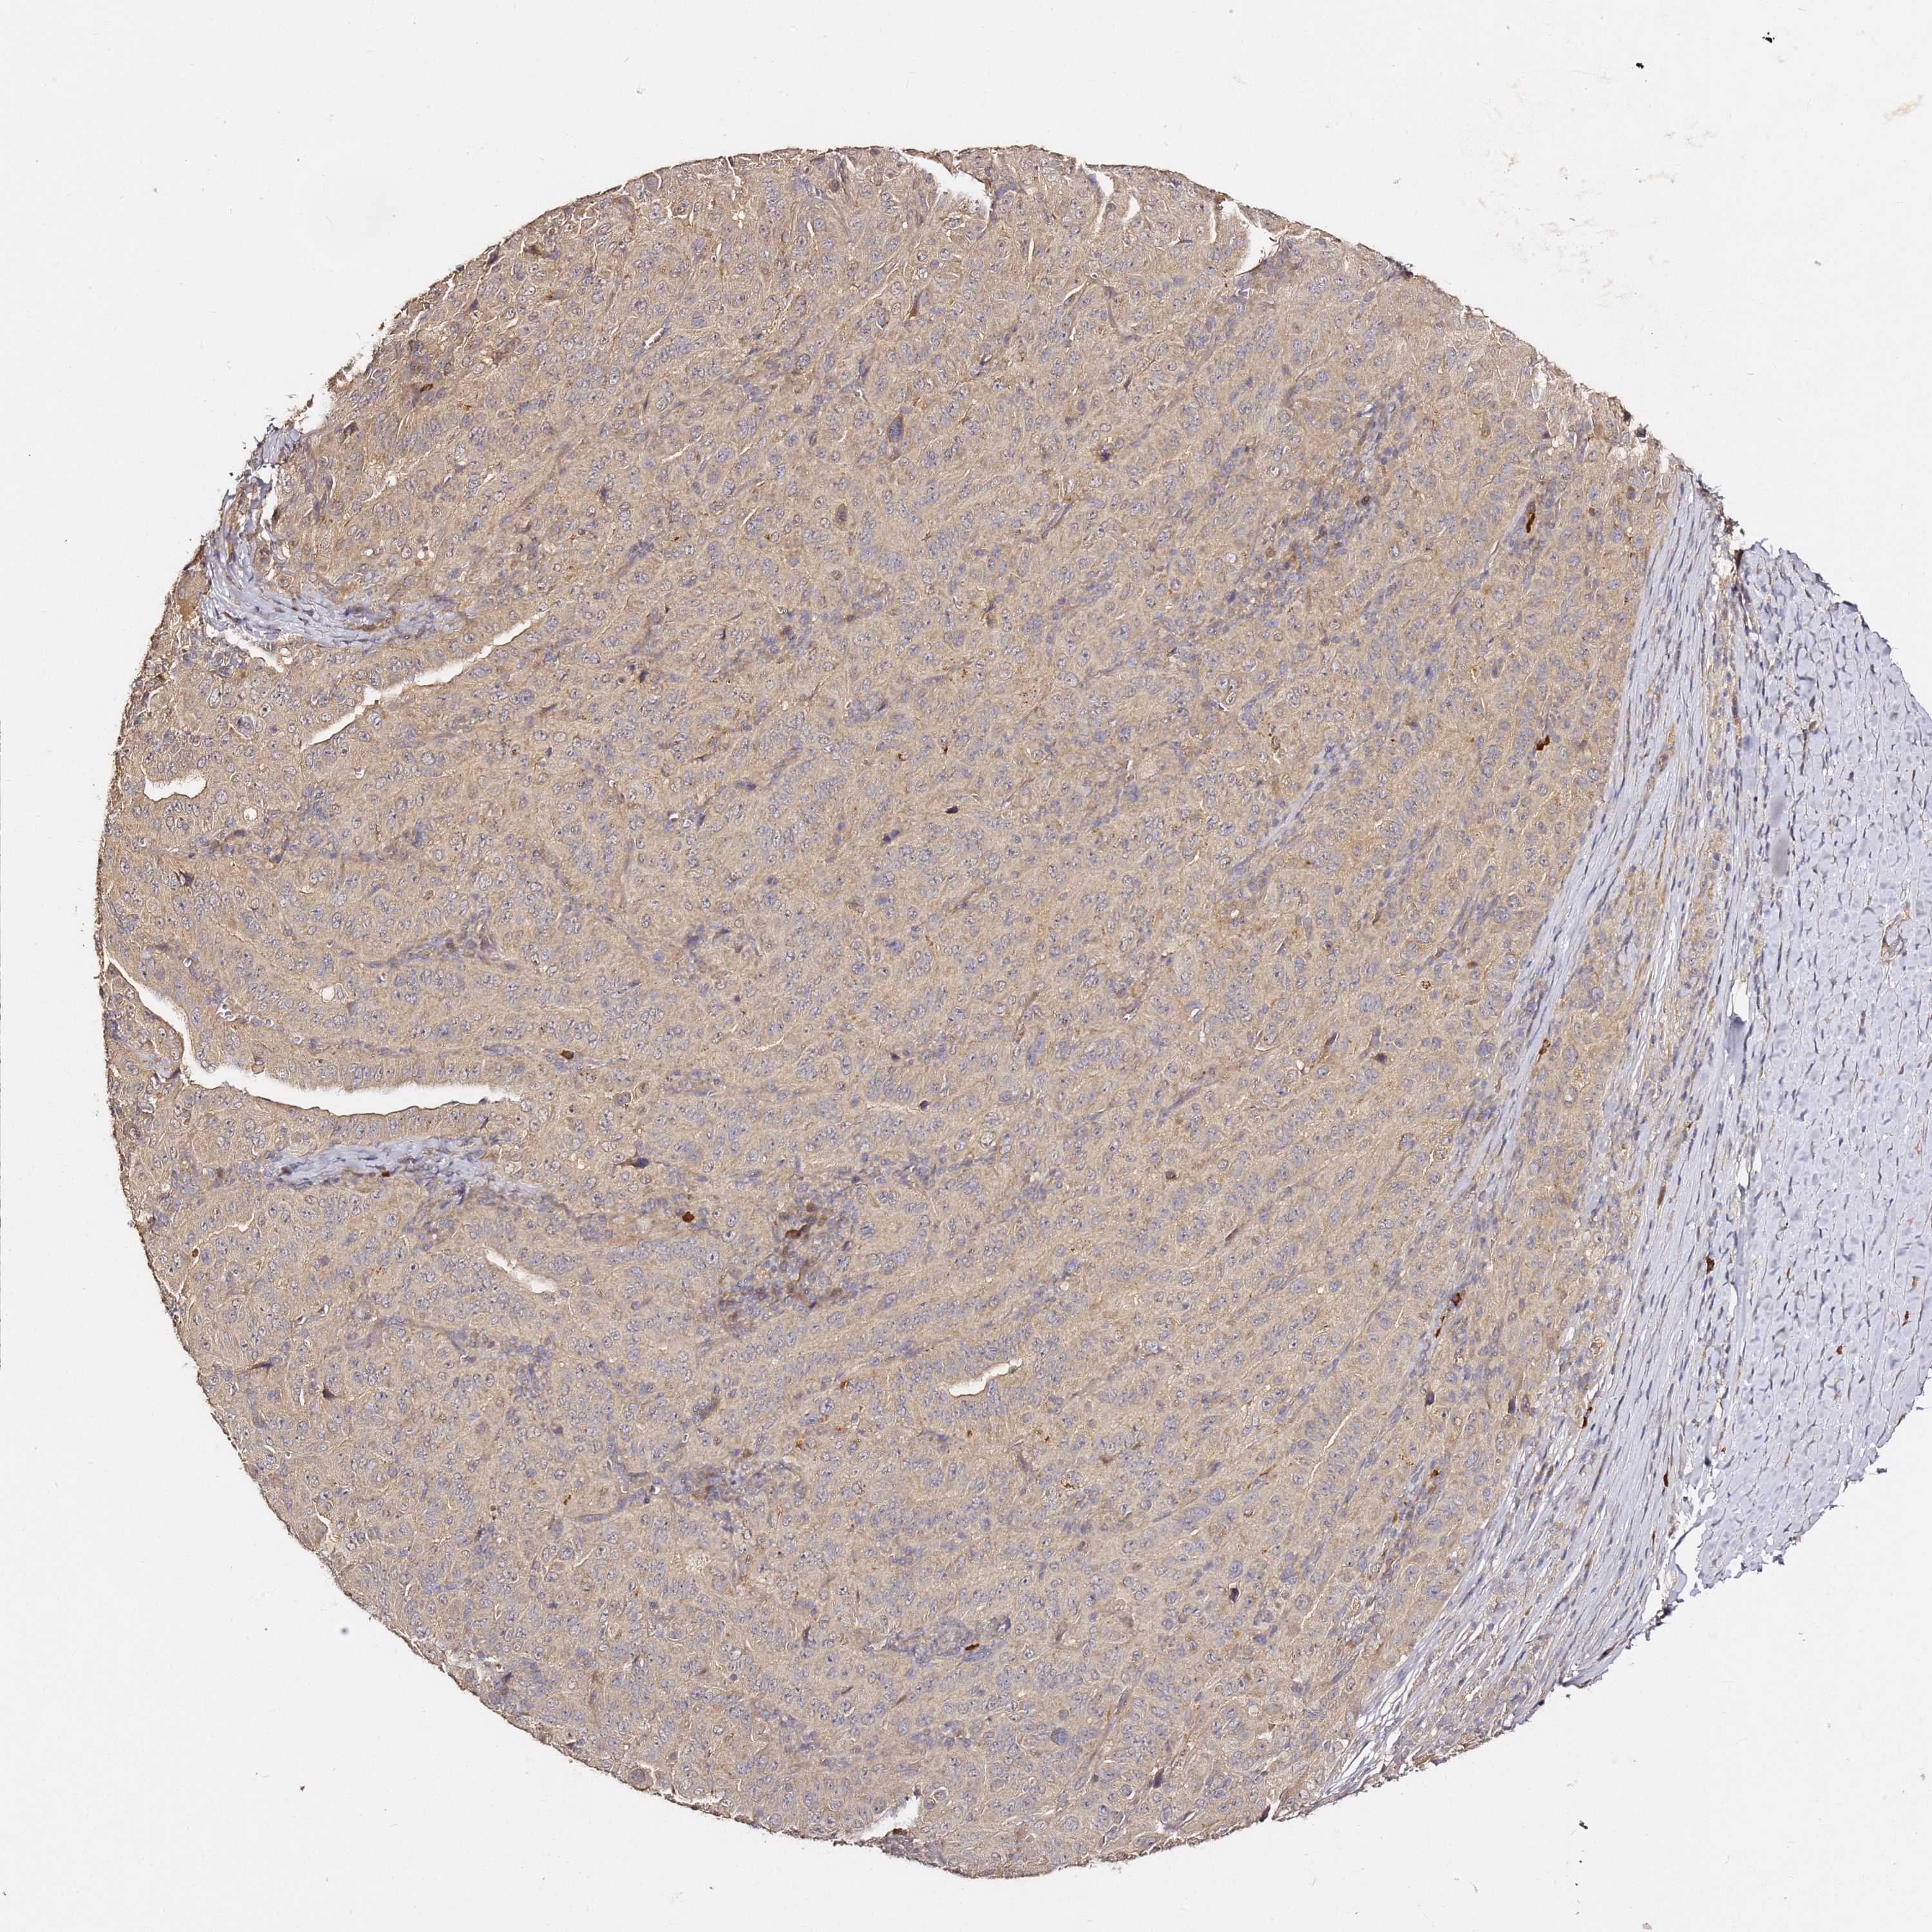

PANCREATIC CANCER - Protein expressioni

A mouse-over function shows sample information and annotation data. Click on an image to view it in a full screen mode. Samples can be filtered based on level of antibody staining by selecting one or several of the following categories: high, medium, low and not detected. The assay and annotation is described here.

Note that samples used for immunohistochemistry by the Human Protein Atlas do not correspond to samples in the TCGA dataset.

Antibody stainingi

Antibody staining in the annotated cell types in the current human tissue is reported as not detected, low, medium, or high, based on conventional immunohistochemistry profiling in selected tissues. This score is based on the combination of the staining intensity and fraction of stained cells.

Each image is clickable and will lead to virtual microscopy that enables deeper exploration of all samples and also displays staining intensity scores, fraction scores and subcellular localization as well as patient and tissue information for each sample.

Antibody HPA046804

Staining

High

Medium

Low

Not detected

Intensity

Strong

Moderate

Weak

Negative

Quantity

>75%

75%-25%

<25%

None

Location

Nuclear

Cytoplasmic/membranous

Cytoplasmic/membranous,nuclear

Adenocarcinoma, NOS